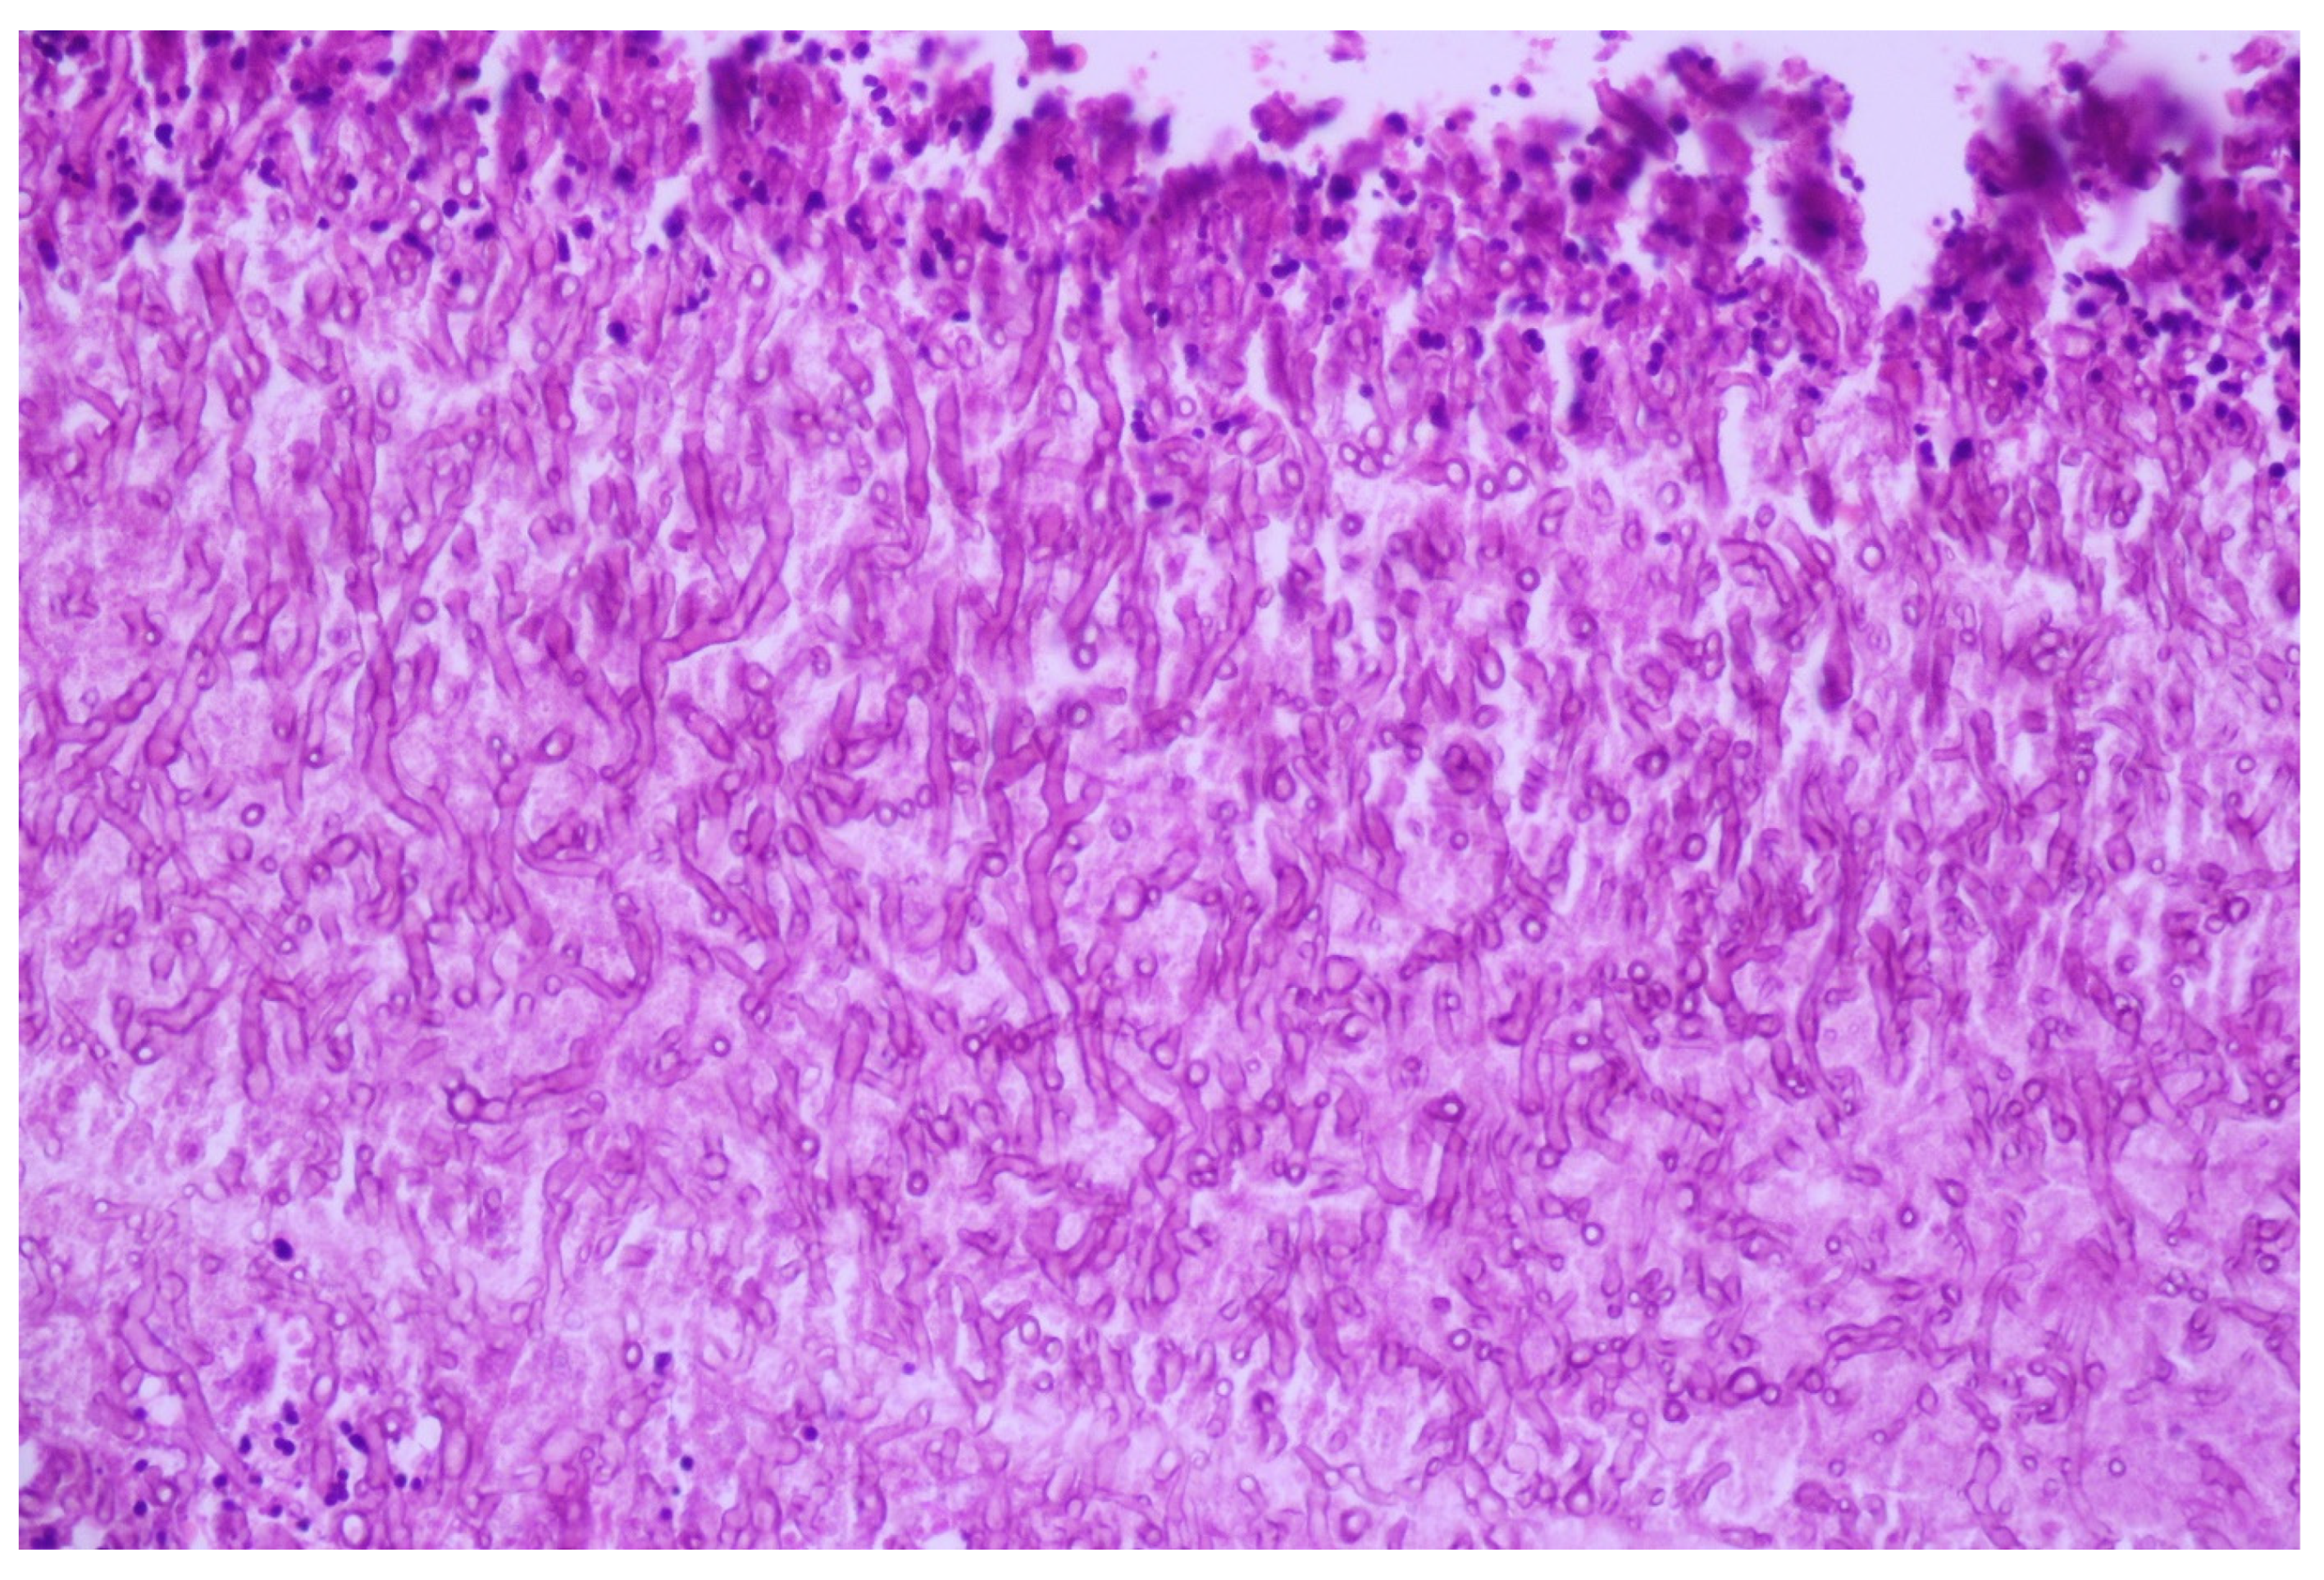

3.1. Case No. 1

3.2. Case No. 2

3.3. Case No. 3

3.4. Case No. 4

4.2.1. Acantholitic Features in Lung Carcinoma

4.2.2. Pseudoangiosarcomatous Feature in Lung Carcinoma